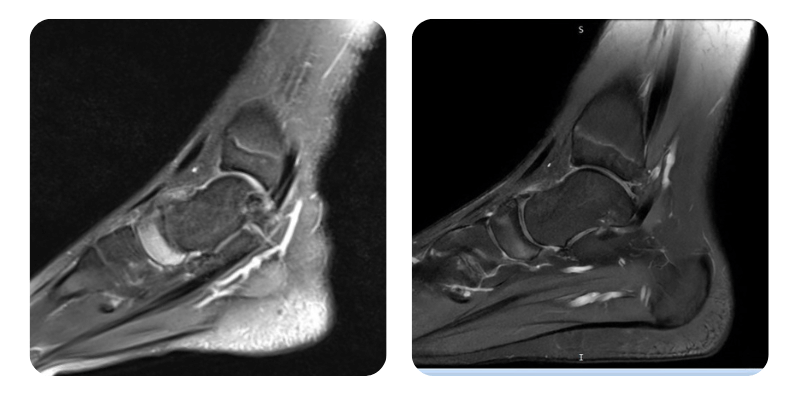

Előtte

Utána

M.M.T., 14 éves – Aseptikus osteonekrózis a bal láb naviculare csontján, Lyme-kór

Anamnézis: A páciens bal lábán aseptikus osteonekrózist diagnosztizáltak a naviculare csont területén. A beteg 7 hónappal ezelőtt bokarándulást szenvedett, amely átmenetileg javult, azonban egy hónapja a fájdalmak visszatértek. MRI-vizsgálat igazolta az elváltozást. A fájdalom intenzitása 6–7/10, főként reggel. Nincs krónikus gyógyszeres kezelés, nincsenek ismert személyes előzmények.

Lefolyás: Kontrollvizsgálaton a páciens elmondja, hogy a fájdalom szinte teljesen megszűnt (1/10 az eredeti 6–7/10-hez képest), a mobilitás javult. A kontroll-MRI kb. 70%-os ödémacsökkenést mutat.